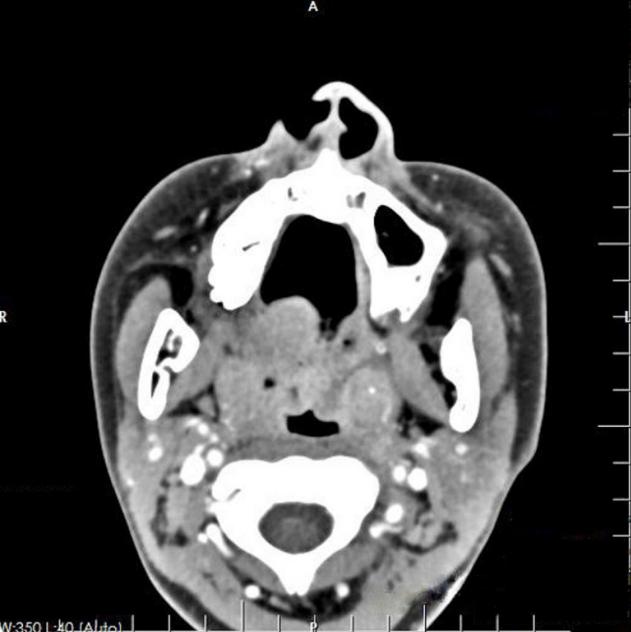

一名13岁女孩诉咽痛2个多月,伴有间歇性发热。入院前被当地医院诊断为化脓性扁桃体炎,并否认有抽搐或昏迷、恶心、呕吐或吞咽困难的病史。自发病以来,食欲和睡眠质量都很差。鼻咽镜检查显示咽部有一个溃疡病变肿块(图1)。增强计算机断层扫描(CT)显示悬雍垂轻微肿胀,双侧扁桃体增大(图2)。在没有手术禁忌症的情况下,获得父母的书面知情同意后,于全身麻醉下进行了扁桃体活检。

图1 鼻咽镜检查显示咽部有溃疡病变

图2 增强CT显示悬雍垂轻度肿胀,双侧扁桃体增大,左侧扁桃体点状钙化